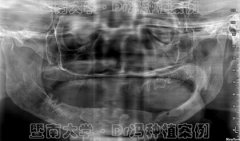

目前,种植牙技术已经相当成熟,尤其是人工智能数字化种植牙技术更是为缺牙...

种植牙是目前很受欢迎的缺牙修复方式,不少缺牙者牙槽骨严重萎缩、骨量极少...

种植牙是最佳的缺牙修复方式已经是不争的事实!但对骨质疏松、牙槽骨薄如指...

穿颧种植技术一直被誉为是种植牙界珠穆朗玛峰式的顶级技术,也是很好的疑难...